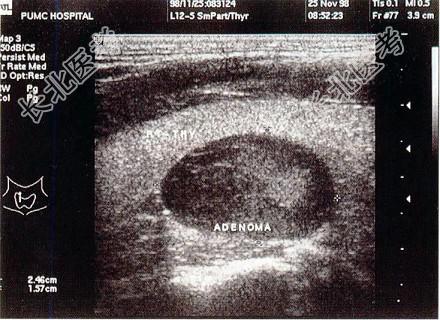

- 单项选择题患者颈部包块5年,结合超声声像图, 最可能的诊断是   (   )

A、甲状腺结节

B、甲状腺瘤

C、甲状腺癌

D、甲状腺炎

E、桥本氏甲状腺炎